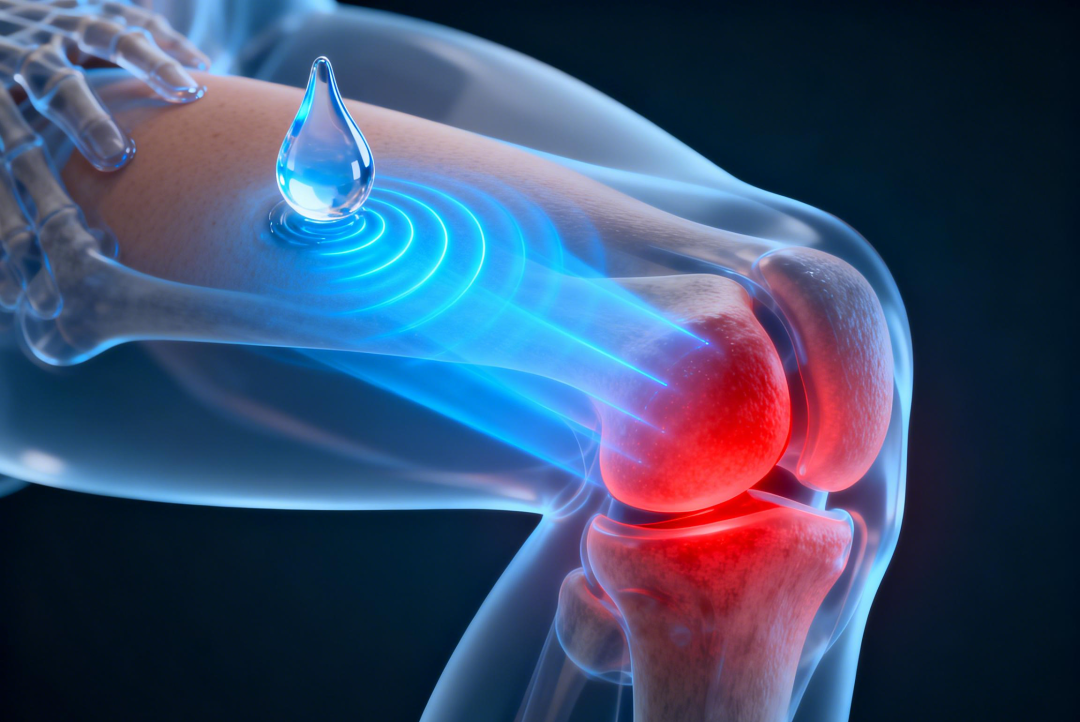

镇痛刚需井喷: 老年群体是骨关节炎、风湿痛、颈肩腰腿痛的重灾区。但老年人往往基础疾病多、肠胃脆弱,传统的口服非甾体镇痛药极易引发严重的胃肠道不良反应。因此,安全性更高、起效更快的外用镇痛制剂(如高端乳胶剂)正迎来爆发式的需求增长。

局部外用剂型可直接穿透皮肤直达炎症靶点,起效快、全身副作用低,适用于运动损伤、劳损、关节炎等常见疼痛场景,是家庭常备、临床常用的刚需品类,市场需求持续刚性。

普利制药已布局双氯芬酸系列核心产品:双氯芬酸钠肠溶缓释胶囊、双氯芬酸钠缓释片,与本次获批的外用乳胶剂(20g+50g 双规格)形成 “口服 + 外用”“小剂量 + 大剂量” 全场景抗炎镇痛解决方案。产品线协同优势可助力渠道快速拓展终端,形成差异化竞争壁垒。